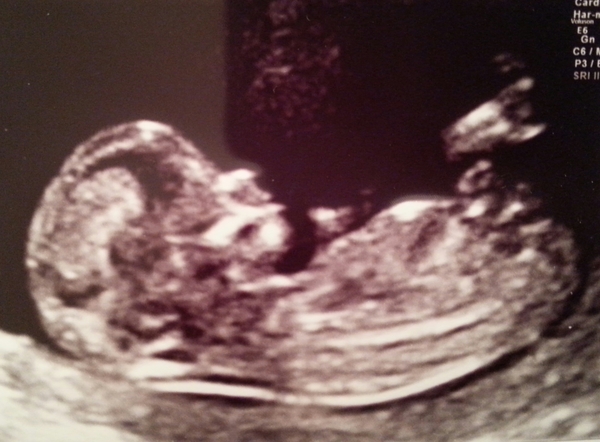

Superexcited · 08/04/2015 13:45

I have been for my scan and all was well. I was dated at 13+0 which is a few days more than I expected.

Baby was very active and it took the sonographer a long time to get all of the measurements. Here is the bubba.